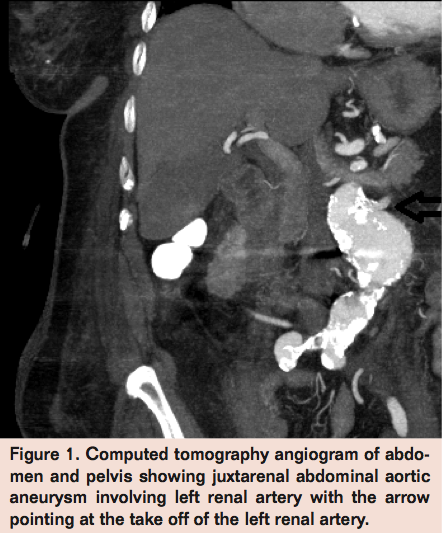

The patient was placed supine and endotracheal intubation was induced. Under ultrasound guidance, both common femoral arteries were cannulated. An 8 Fr sheath was used in the right common femoral artery and an 11 Fr sheath used in the left common femoral artery. The left brachial artery was then cannulated with a 6 Fr Destination sheath (Terumo) under ultrasound guidance. A Glidewire was then carried down the descending thoracic aorta with a vertebral catheter. A sheath was then introduced and positioned above the level of the renal arteries and an aortogram was obtained, noting the origins of the renal arteries and confirming the takeoff of the left renal artery from the AAA situated about 13 mm below the level of the right renal artery.

Subsequently, the Endologix endograft, with a main body diameter of 22 mm, a length of 70 mm, and an iliac limb length of 30 mm, was advanced from the left groin. The contralateral limb was snared and pulled down proximal to the right iliac bifurcation (Figure 2). The aorta at the level of the right renal artery was normal. The left renal artery was then selectively cannulated and a 6 mm x 59 mm ICAST covered stent (Atrium) was deployed with the proximal end at the level of the right renal artery. The ICAST stent was used because it provides a superior radial force as compared to VIABAHN (Gore) but is potentially less rigid than the FLUENCY stent (C.R. Bard). The decision to utilize ICAST was based on favorable experience with the stent in previous similar situations. Two additional aortic cuffs that were 25 mm in diameter and 95 mm in length with generous overlap were additionally used to extend the graft up to the level of the right renal artery. The goal of this was to minimize the risk of type I endoleak, covering the origin of the left renal artery which had the “chimney” stent in place.